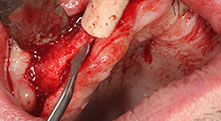

A 40-year-old patient with very poor residual dentition wanted an implant-based restoration. Because he is a smoker, a sinus lift in the maxilla with a fixed denture was contraindicated. A bar denture on four anterior implants was planned.

Piezomed B6

The alveolar ridge was split on both sides by piezo surgery (instrument: Piezomed B6). The implants were placed in the same procedure and the peri-implant bone was additionally built up using the GBR technique.